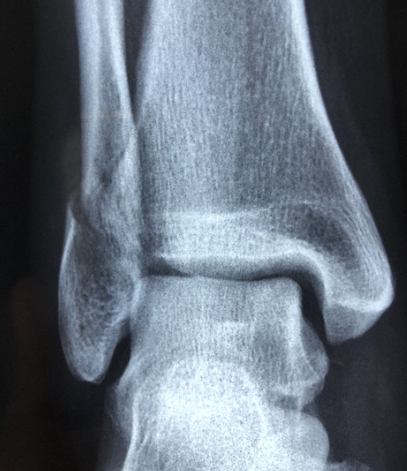

또한 엑스레이 검사를 통해서 골다공증으로 인한 압박 골절 등도 알 수 있습니다.

골절의 확률이 높아집니다. 심한 경우 기침 등의 일상생활에서도 뼈가 쉽게 부러질 수 있습니다.

50대 ~70대 여성은 주로 손목 골절에서부터 먼저 발생하며, 70대에는 고관절이나 척추의 골절이 흔하게 발생합니다.